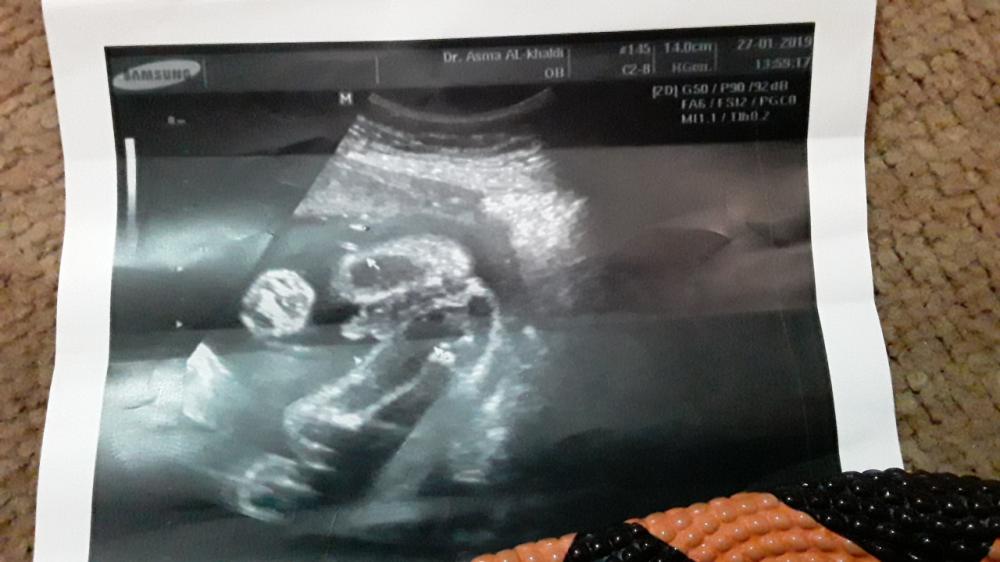

هذا سوناري بالاول اقتنعت لما قالت لي الدكتوره بنت بعدين بالمراجعه اللي بعدها قالت ولد لانها شايفه انتفاخ بين الرجول بس م قدرت تاخذ صورة لانه يتحرك كثير فحطيت ببالي انه ٥٠ بالميه ولد ويارب يحقق مرادي

انا اربع اخصائية حكو ولد

ومبارح دكتورة الحكومة حكت بنت

واليوم روحت اخصائية حكت الحمد لله ولد

وهاي صورة اليوم

ترانيم واضح جدا انه ولد ما شاء الله

حبيبتي هذا ظهرلي عضو ذكر اتمنى يخطىء معي لاني في الشهر الرابع قالولي بنت و انا أتمنى ولد لاني عندي بنت 😁و الحمد لله على نعمته